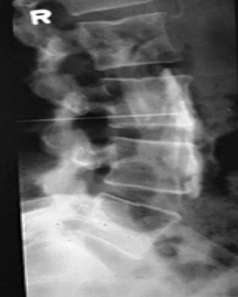

The Lumbar Sympathetic Nerve Block is a procedure used to block or decrease pain in the lower extremities caused by injury or disease of the sympathetic nervous system. The lumbar sympathetic nerves are located on either side of the lumbar spine (lower back).

The Lumbar Sympathetic Block is an outpatient procedure, usually done in the Operating Room or a Special Procedure Room. For your safety and comfort, you will be connected to monitoring equipment (EKG monitor, blood pressure cuff, and a blood-oxygen monitoring device), and positioned on your stomach. The doctor or nurse may start an intravenous line and give some medicine to help you relax. Your back is cleansed with an antiseptic soap after which the doctor injects numbing medicine deep into your skin and tissue. This will cause a burning sensation for a few seconds. After the numbing medicine takes effect, the doctor will insert a another needle and, with the assistance of a special X-ray machine called a fluoroscope, inject a radiopaque dye (contrast solution) to ensure the needle is in proper position. With the needle in position, a small mixture of numbing medicine (anesthetic) and anti-inflammatory medicine (steroid) is injected. After the procedure, we ask that you remain at the Clinic until the doctor feels you are ready to leave.